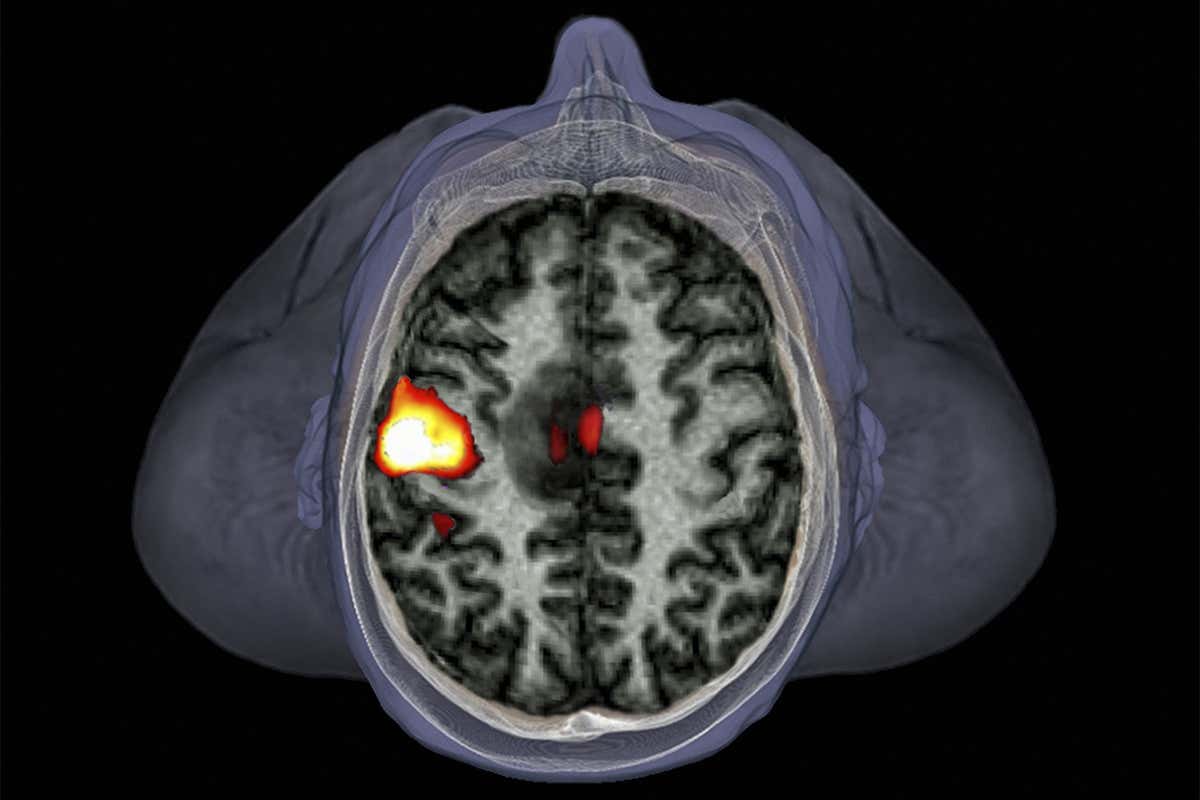

How sound are fMRI brain studies? Zephyr/Science Photo Library

The use of fMRI is a common method for scanning the brain in neuroscience and psychology experiments. To make sense of the data produced, researchers sometimes use a technique called spatial autocorrelation to identify areas of the brain that appear to “light up” during particular tasks or experiences. But some software flaws in the popular fMRI data analysis packages SPM, FSL and AFNI meant this technique routinely produced false positives, resulting in errors 50 per cent of the time or more.

The types of study most likely to be affected are those that are usually reported with headlines along the lines of “X causes part Y of your brain to light up”, or “This is your brain on drug Z”. Those that show relatively weak statistical associations are the likeliest to be inaccurate – whereas studies reporting strongly significant findings may ultimately still be sound.